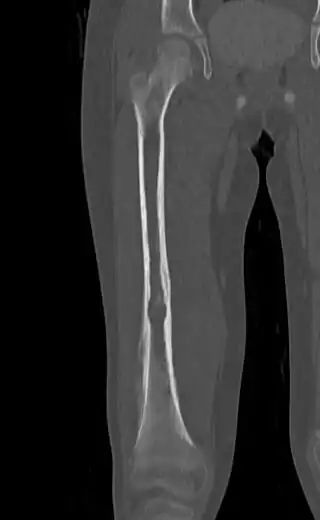

![]() ![]() | |

| Top: Ewing sarcoma of the thigh bone on a child's CT scan Bottom: Extraskeletal Ewing sarcoma of the hard palate | |

It can occur anywhere in the body, but most commonly in the pelvis and the long tubular bones, especially around the growth plates.[1] The diaphyses of the thigh bone are the most common sites, followed by the tibia and the upper arm bone. Around 25% have spread at presentation.[1] In soft tissue, it can affect a wide distribution of the body.[6] Rarely, it can develop in the cervix, vagina and vulva.[10]